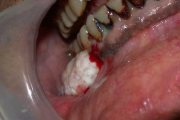

Suu limaskesta haavandid

- Alati tuleb kontrollida hambaproteese. – Haavandi põhjuseks võib olla odontoloogiline infektsioon. – Igal juhul tuleb arvestada vähi võimalusega. Reeglina tuleb võtta biopsia haavanditest, mis kahe nädala jooksul ei parane. – Konsulteerida hambaarstiga; patsiendid, kellele tuleb teha Loe edasi »